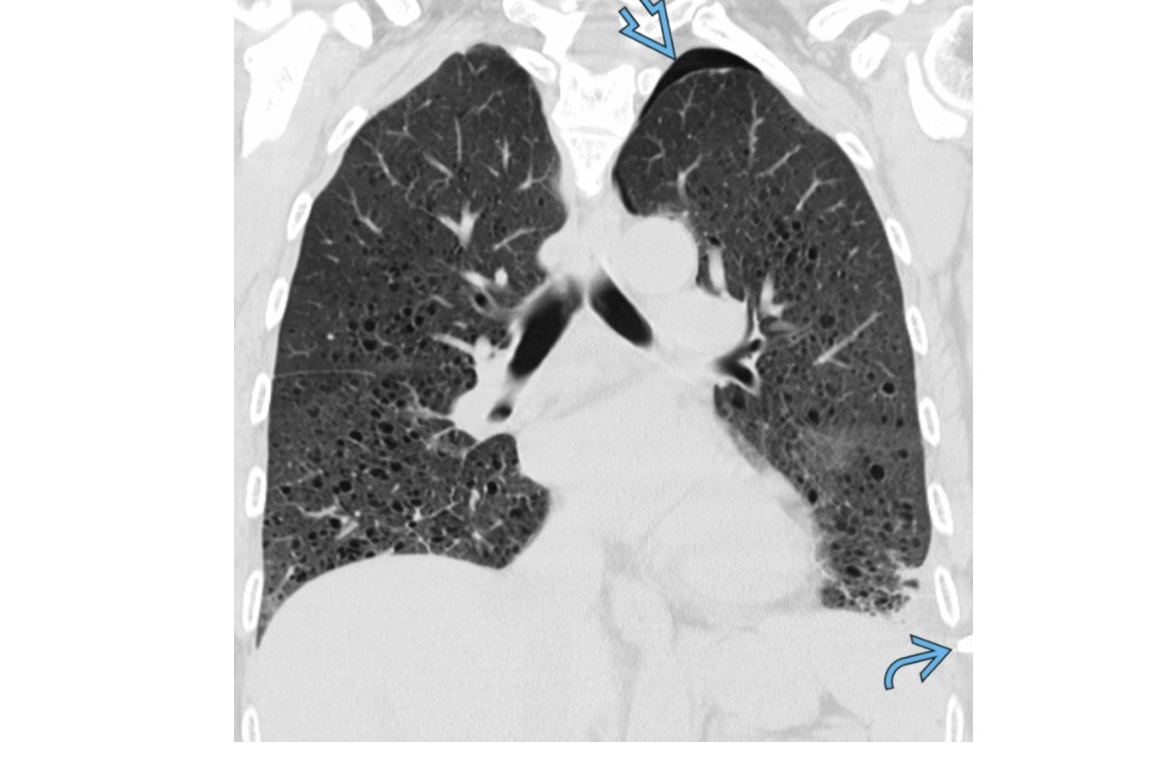

UIP

CXR

Reticular or reticulonodular opacities

Subpleural/peripheral; mid and lower lung zones

Macrocystic Honeycombing (strongest predictor)

Basilar predominant

Traction bronchiectasis

Subpleural reticulations

smoking association

Causes

- connective tissue disease such as RA

- asbestosis

- Drugs (amidorane, nitrofurantoin, methotrexate)

- IPF (diagnosis of exclusion)